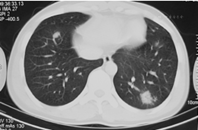

21例患者均行肺电子计算机断层扫描(CT)检查,提示双肺单发(2例)或多发(19例)的斑片状、条片状、团片状、结节状、磨玻璃样高密度影,边界模糊,其中2例病灶中出现含气支气管影。单个病灶直径1~5 cm,可为单肺(9例,其中5例为右肺,4例为左肺)或双肺(12例)受累,在肺叶、段分布上无明显特异性(图1、图2、图3)。

本组病例中,患者年龄主要集中在20~40岁,既往健康情况良好,大部分患者表示既往有麻疹疫苗接种史,但均不能提供末次麻疹疫苗接种时间。患者病程自限,热程均在一周以内,平均热程为(4.5±1.7)d,1例患者仅发热半天。患者发热多在出疹后3 d内迅速退热,状态良好,除肺炎外,其他并发症相对较少且轻,仅1例患者有一过性轻微腹泻,5例患者肝功能轻度异常。患者白细胞计数正常或偏低,提示为病毒性感染。肺炎为本研究中所有患者的主要临床表现,影像学上突出表现为单发或多发的团、片状高密度影,在肺叶、段的分布上无特异性,病灶直径1~5 cm。国内对聚集性流行的不典型麻疹研究发现,成人的肺炎检出率为19.5%~54.9%(经X线检查诊断)[5,6,7],如进行肺部CT检查,则肺炎的检出率则升至31.2%~94.1%[5,7];散发的成人麻疹(包括典型麻疹病例)中肺炎检出率为6.1%~24.1%(经X线检查诊断)[8,9]。国外报道成人麻疹中,肺炎发生率为34%[10]。然而,上述研究显示,不典型成人麻疹患者尽管并发肺炎的概率较高,单个病灶范围可以较大,但咳嗽、胸痛、呼吸困难等症状不重,且病变吸收较快,患者通常一般状态佳,病程自限、预后良好[5,10],本研究结果与之相似。